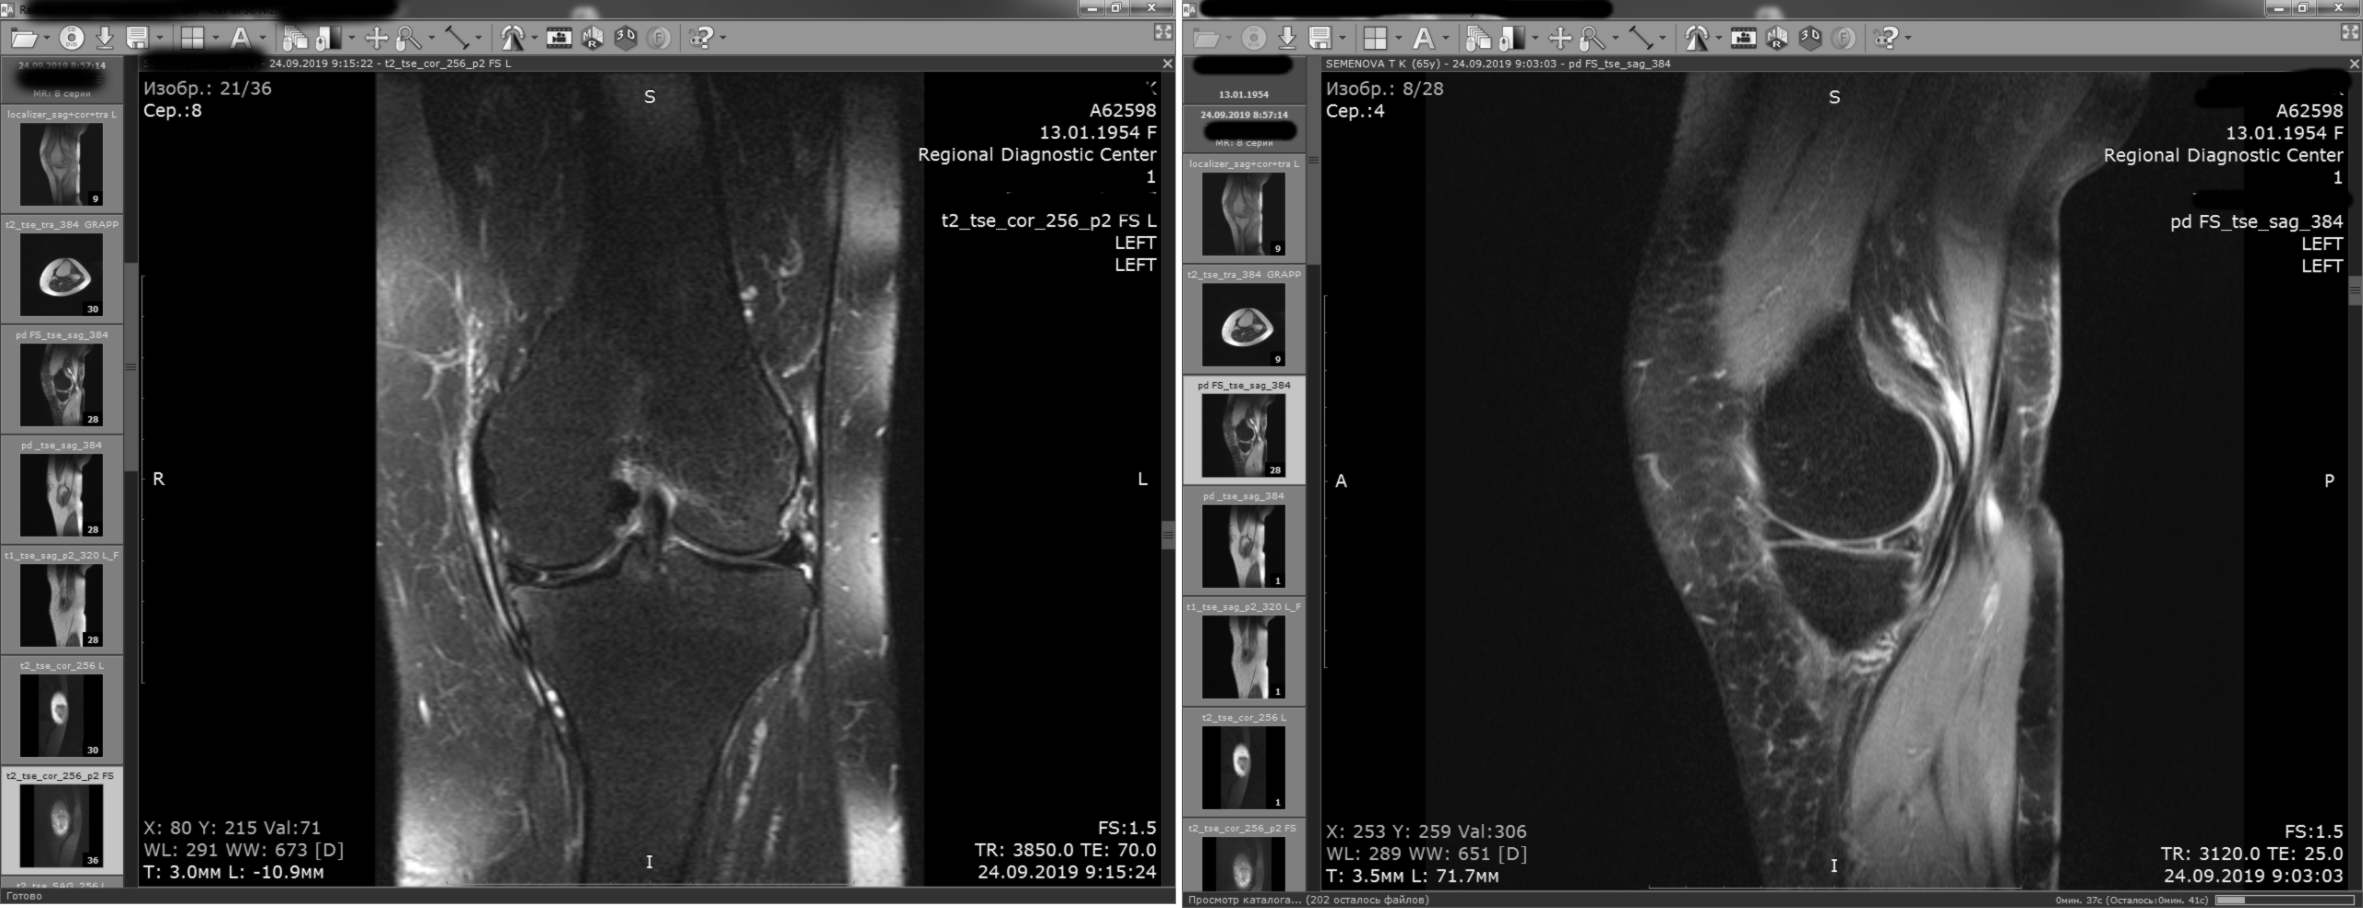

и спустя 2 месяца после операции

|